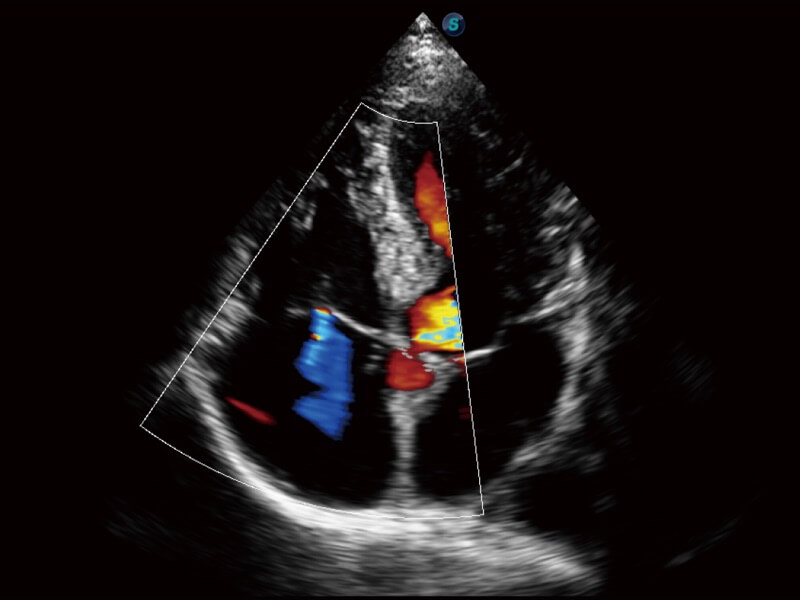

Die Bildqualität liegt immer im Zentrum definierter klinischer Ergebnisse. ELITE liefert eine leistungsstarke und klare Bildgebung, die durch eine leistungsstarke Architektur, hochmoderne Sonden und ausgeklügelte Verarbeitungsalgorithmen erzeugt wird, für ein höheres Maß an Klarheit und Vertrauen.

Ultraschall wird immer vielseitiger und übernimmt immer mehr klinische Aufgaben. Als Vorreiter, der Ärzten dabei hilft, mehr zu erreichen, ist ELITE mit einer umfassenden Palette fortschrittlicher Funktionen für die Allgemeine Bildgebung, Gynäkologie/Geburtshilfe, Kardiologie und mehr integriert.

Ultraschall wird immer vielseitiger und übernimmt immer mehr klinische Aufgaben. Als Vorreiter hilft ELITE den Ärzten dabei, mehr zu erreichen, indem es mit einer umfassenden Palette fortschrittlicher Funktionen ausgestattet ist, die die allgemeine Bildgebung, die Geburtshilfe/Gynäkologie, die Kardiologie und vieles mehr abdecken.